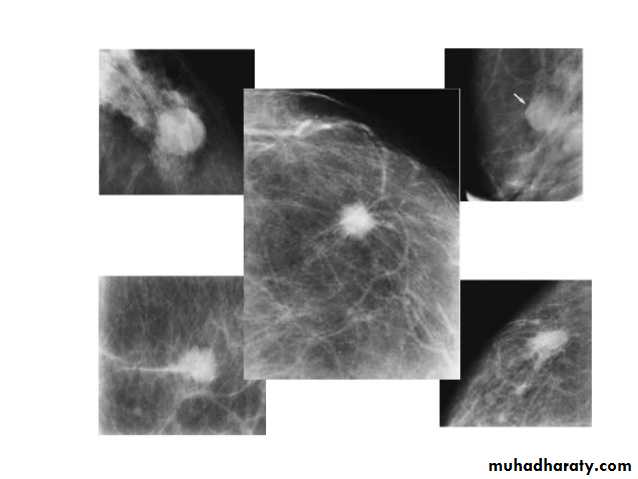

Solid benign (non-cystic lesion) fibro adenoma

Fibroadenoma is a common benign breast lesion and results from excess proliferation of connective tissue. Fibroadenomas characteristically contain both stromal and epithelial cells.Mammography

Fibroadenomas have a spectrum of features from the well circumscribed discrete oval mass hypo- or isodense to the breast glandular tissue, to a mass with macrolobulation or partially obscured margin. Involuting fibroadenomas in older, typically postmenopausal patients may contain calcification, often producing the classic, coarse popcorn calcification appearance.

FIBROADENOMA